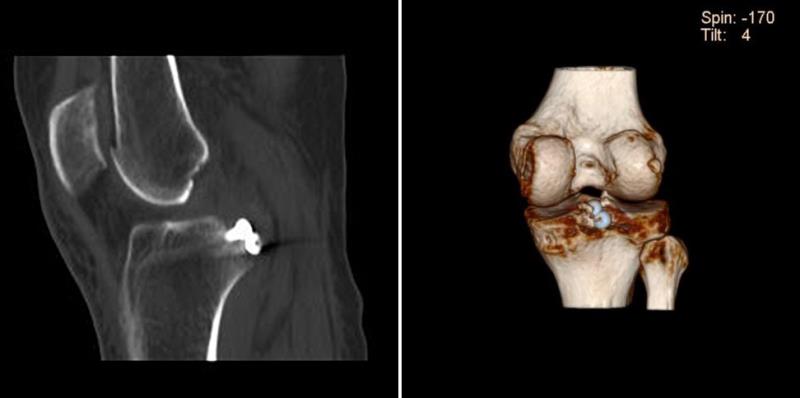

关节镜下在后交叉韧带胫骨止点撕脱骨折块上植入2枚空心螺钉